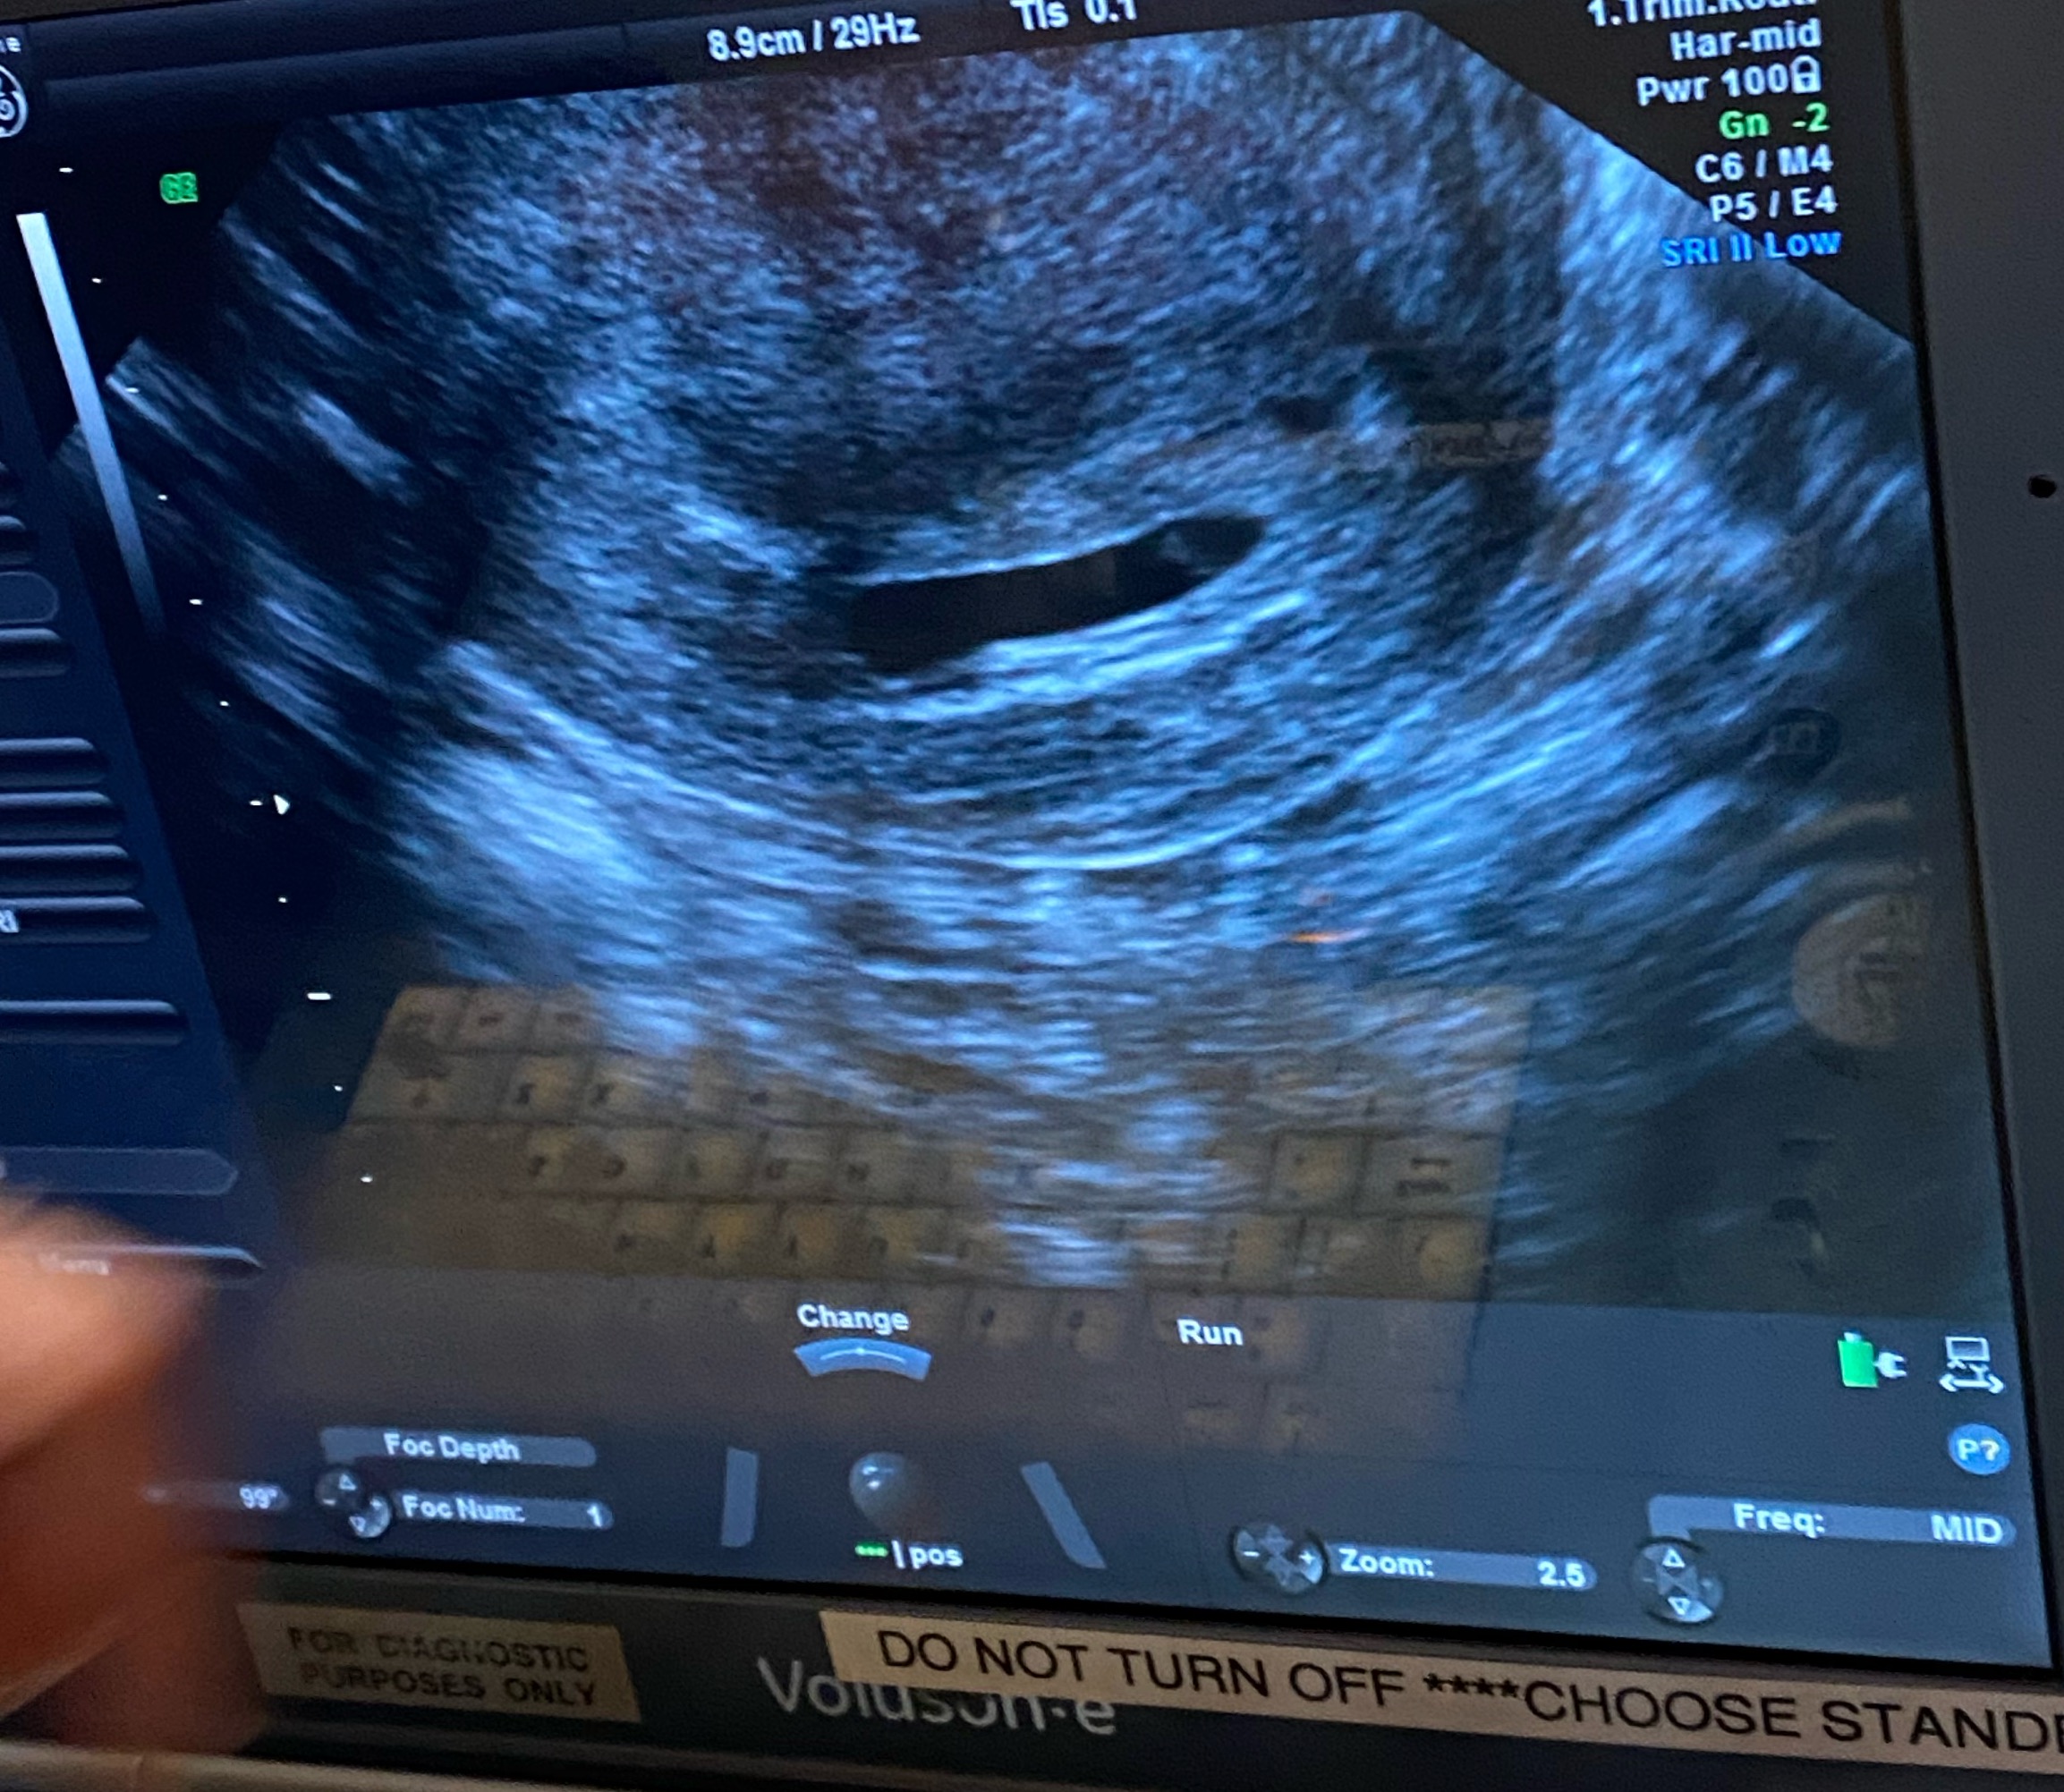

Had my transvaginal scan today at 6 weeks 1 day. Doctor said it was too early for hearing the heartbeat, but we could see the baby move and a heartbeat on the screen ( heart rate 109). We confirmed it was not an ectopic. I’d now go back at 8 weeks for another scan.

Any ramzi guesses on gender? Attachment 43225